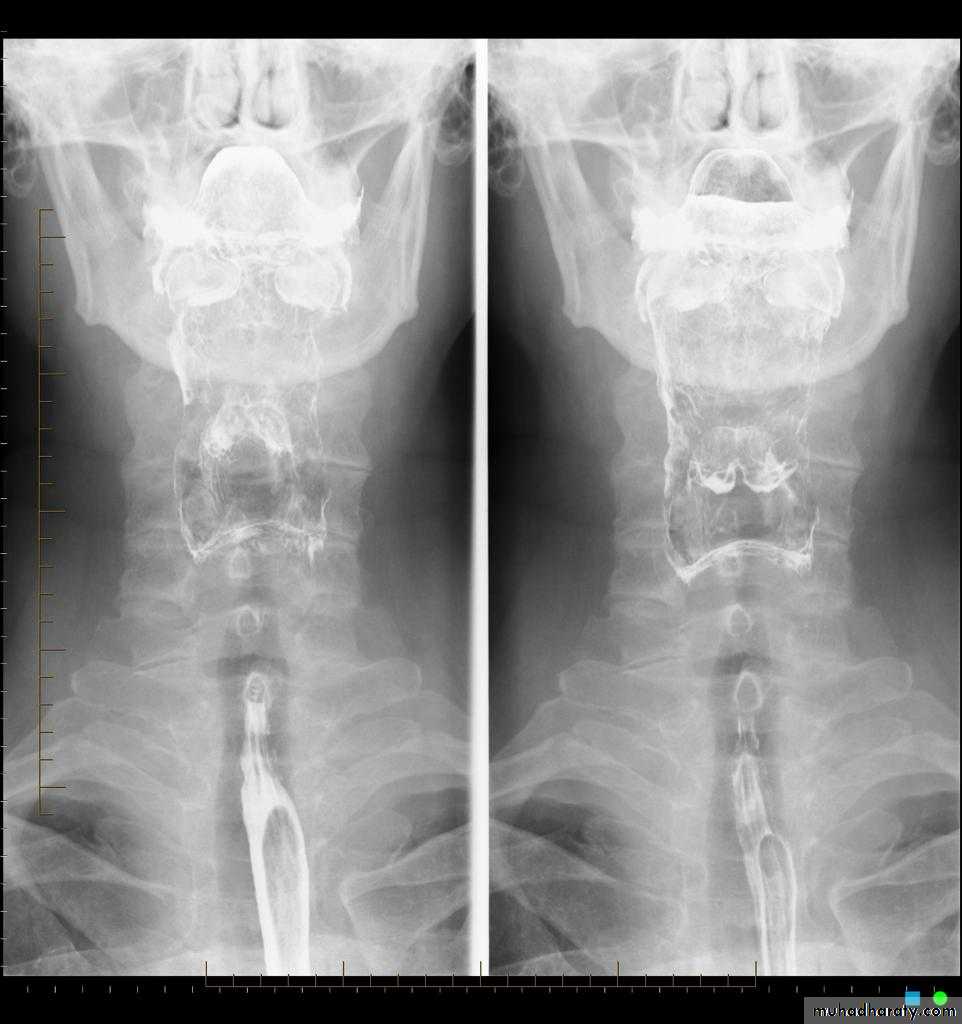

Figure 2: normal barium swallow of esophagus.